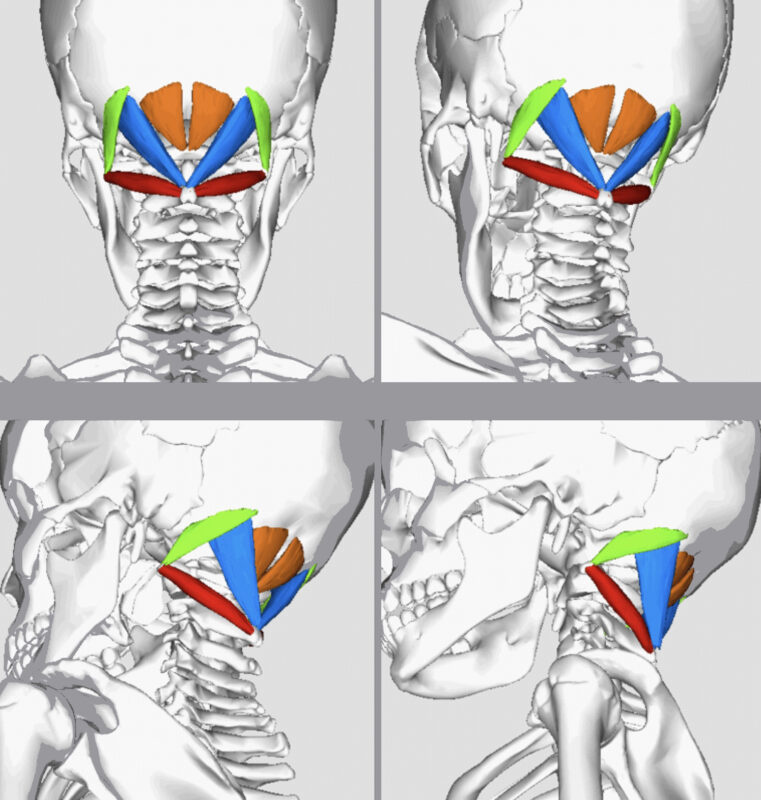

Υπάρχουν πολλοί μύες στον αυχένα που υποστηρίζουν το βάρος του κεφαλιού σας και βοηθούν στη σταθεροποίηση των πολύ κινούμενων αυχενικών αρθρώσεων.

Το ινιακό, με απλά λόγια, είναι το πίσω μέρος του κεφαλιού. Οι υπινιακοί μύες είναι οι μύες που βρίσκονται στον ινιακό.

Οι μύες τείνουν να καταπονούνται αν κάνουν περισσότερα από αυτά που έχουν ρυθμιστεί επί του παρόντος να κάνουν. Ένα καλό παράδειγμα αυτού μπορεί να είναι να κάθεστε σε έναν υπολογιστή για 8-10 ώρες την ημέρα. Σε αυτό το παράδειγμα οι μικροί μύες της στάσης μπορεί να αρχίσουν να κουράζονται και το κεφάλι αρχίζει να πέφτει. Για να το αποφύγουμε αυτό, λυγίζουμε ελαφρά το κεφάλι προς τα πίσω και κρατώντας αυτή τη θέση για μεγάλο χρονικό διάστημα π.χ. όταν βρίσκεστε στο γραφείο σας ή σε μια μεγάλη βόλτα με ποδήλατο, μπορεί να οδηγήσει σε σύσφιξη των μυών και πόνο στο κεφάλι.

Αν και αυτός ο τύπος κεφαλαλγίας ανταποκρίνεται σε θεραπεία που προσανατολίζεται στη θεραπεία των περιορισμών των μαλακών ιστών, η μέθοδος εξέτασης, αξιολόγησης και θεραπείας πρέπει να είναι συγκεκριμένη για τον αυχένα και τον ινιακό.